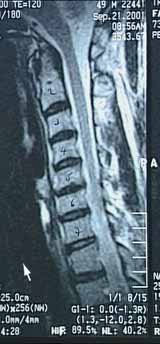

Wurzelsyndrome der Halswirbelsäule

Bei einer DH zwischen dem 5. und 6. Halswirbel wäre die sechste Nervenwurzel betroffen.

Führen Sie den Mauszeiger über das Bild um die Hernie zu sehen.